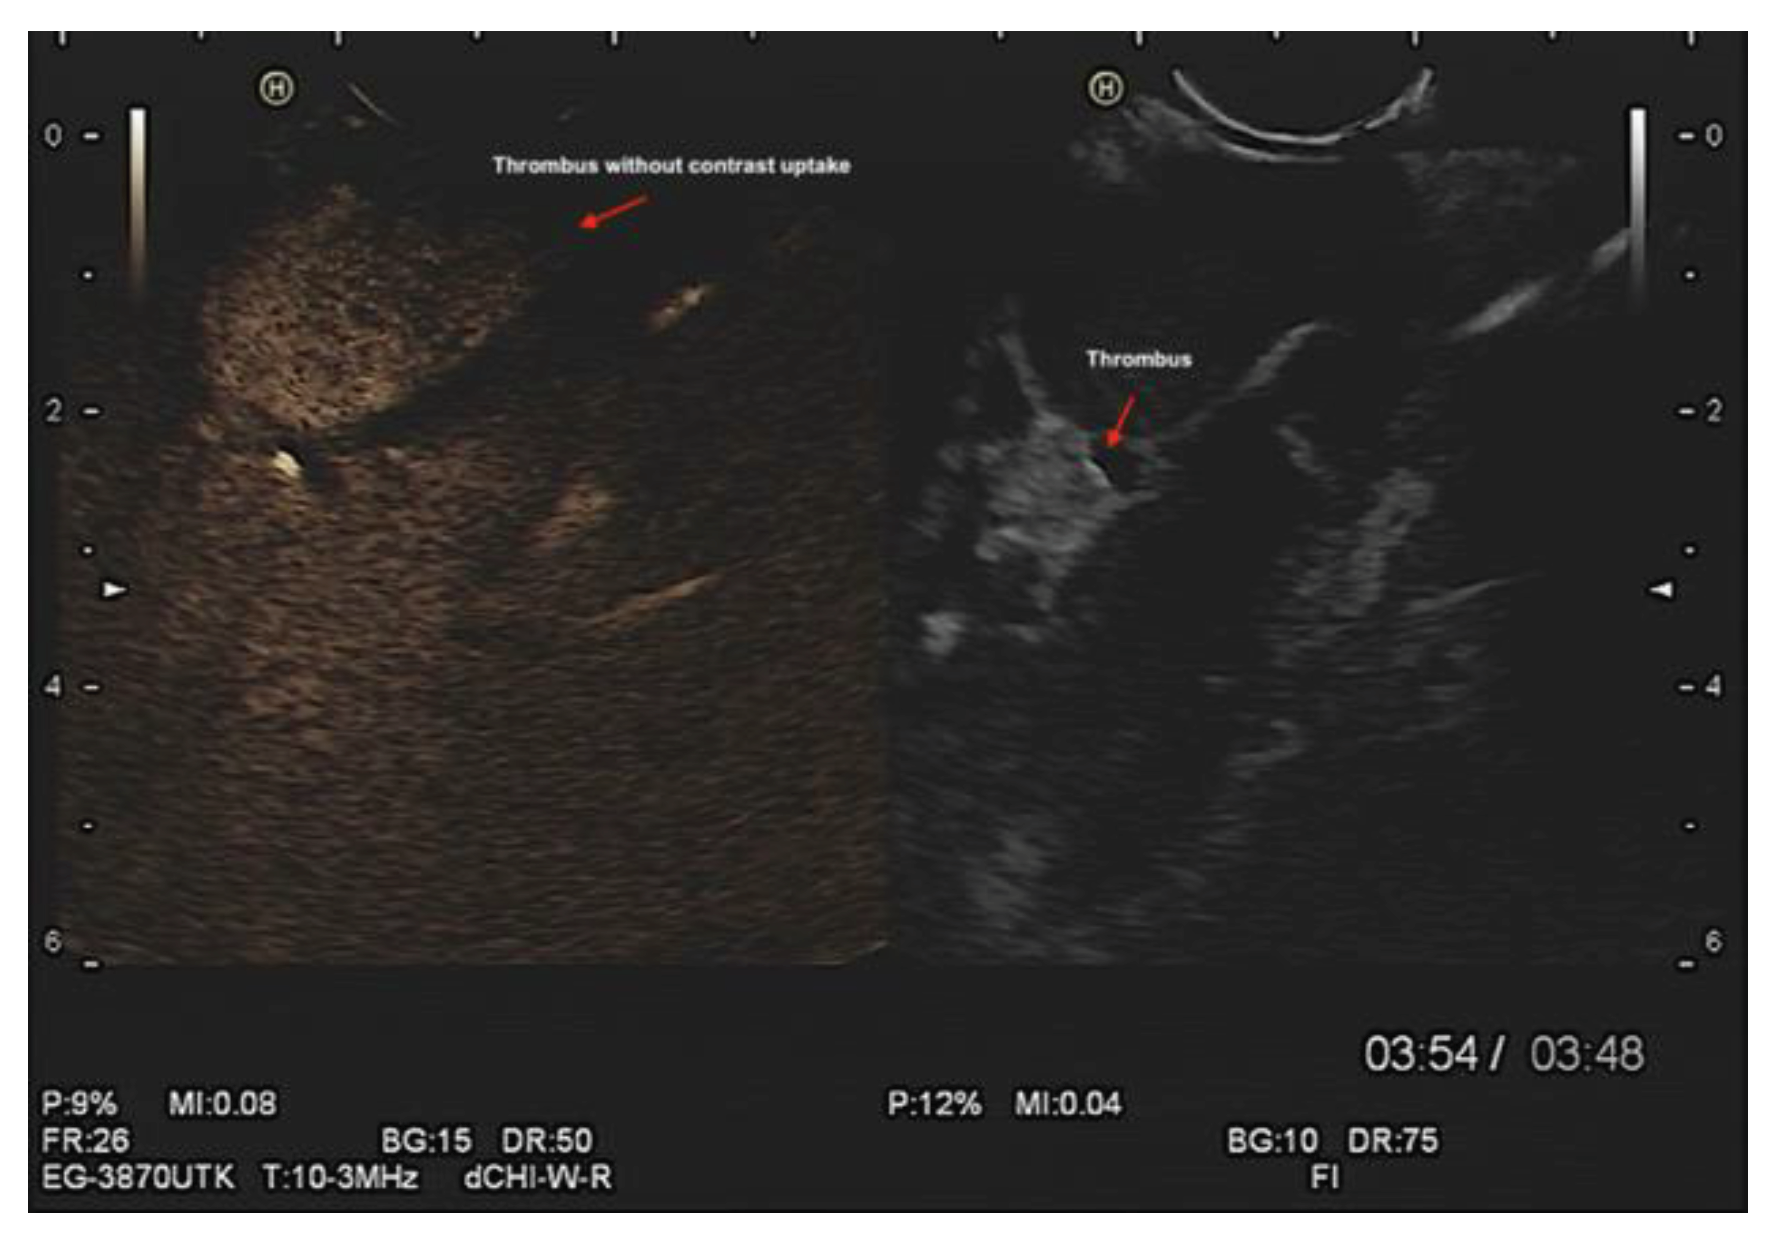

Left atrial appendage (LAA) morphology, thrombus/ myxoma, fibroelastoma, etc. (Figure 5 and Videos 7–9). In addition, contrast endosonographic ultrasound can be used to image vascularity and vessel patterns in an organ of interest, especially for small volume and slow velocity blood flow. Consequently, EUS can differentiate both thrombus and myxoma not only by their distinguishing features of size, origin, shape, mobility, and prolapse but also by contrast enhancement. Compared with the adjacent myocardium, malignant and vascular tumors are hyper-enhanced, whereas stromal tumors and thrombi are hypo-enhanced [16] (Figure 6 and Supp. Figure S3, and Videos 9 and 10).

Figure 6. Contrast endosonographic ultrasound demonstrated the size and morphology of thrombus in left atrial appendage and its hypo-enhanced charchteristic in the same patient.

Preprints 79537 g006